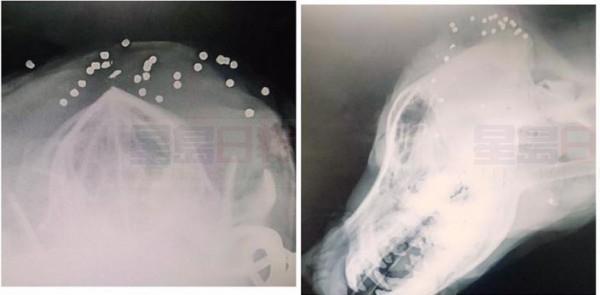

拉布拉多犬Lola原本安穩地生活在家中花園,日前牠的主人Kayla Evans發現牠額頭有一些血跡斑斑的傷口,本來以為是前一晚被夜間出沒的野生動物抓傷,便帶到獸醫診所治理。豈料剃本治理傷口時就看到額頭有好多小洞,不似是野生動物所為,一照X光就發現頭顱裡有好多BB彈,超過粒。醫生為Lola做緊急手術取出七粒子彈,但仍有二十多粒深入肌肉組織和頭骨,有幾粒更在眼睛附近,要取出就要動大手術,亦有損害視力的風險。